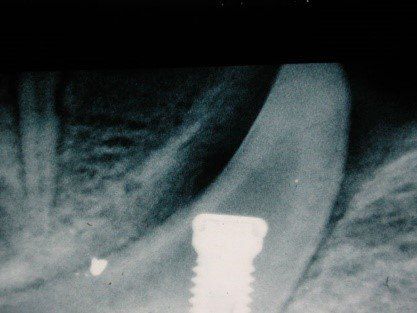

Radiograficamente è visibile il trattamento endodontico dell’incisivo laterale sinistro coinvolto anch’esso nel trauma. Sono visibili inoltre i dispositivi ortodontici necessari pe la sua estrusione al fine di recuperare l’ampiezza biologica, ovvero al fine di mantenere tre millimetri di tessuto dentale sano oltre il margine gengivale